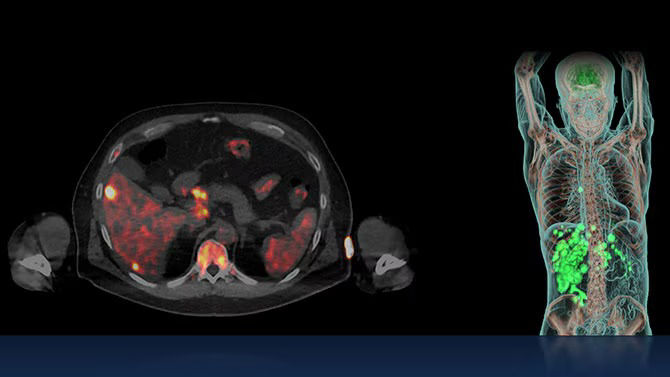

The approach of zeroing in on tumor receptors with positron- and gamma-emitting radioligands to visualize cancer cells, and beta- or alpha-emitting radioligands to destroy cancer cells makes theranostics the quintessential targeted care pathway.

Radioligand therapies have historically been one of the last treatments for cancer, but new evidence shows positive results if this type of care is used earlier, closer to when cancer is diagnosed.² Because of the limited side effects of this precision treatment, it is now a pre-chemo therapy option for some patients.

Episode 4: "New SPECT" for theranostics

Digital CZT SPECT/CT is a major enabler in theranostics. With the ability to identify the bio-distribution and perform dosimetry for therapies like ¹⁷⁷Lu, pioneering clinicians rely on SPECT/CT to monitor therapy.